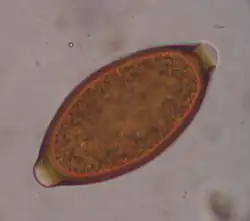

Trichuris vulpis is a whipworm that lives in the large intestine of canines in its adult stages. Out of different types of worms, Trichuris vulpis is one of the smaller worms with a size ranging from 30–50 mm in length. As the name suggests, the worm has a whip-like shape with distinct features including a small, narrow anterior head, which is the digestive part of the worm, and a larger posterior tail, which is the reproductive part of the worm. Eggs from T. vulpis are oval shaped with bipolar plugs and contain a thick outer shell. Their sizes range from 72–90 μm in length and 32–40 μm in width.[1] Because of their thick outer shell, T. vulpis eggs are very resistant to environmental extremes such as freezing or hot temperatures, thus allowing for their long viability in the outside world.[2]

Infection of this parasite can be confirmed with detection of eggs in the canine's feces. Adult T. vulpis females can produce more than 2,000 eggs per day. These eggs can be detected in the canine's feces by the fecal flotation method.[14] This method utilizes the differences of specific gravity of eggs, fecal debris, and the flotation solution.[15] Although these eggs are dense, the use of proper fecal flotation technique using a sugar solution and centrifugation can increase the chances of identifying these eggs in a fecal sample.[16] Multiple fecal samples may need to be tested as the eggs may be shed periodically.[17]

Egg of T. vulpis